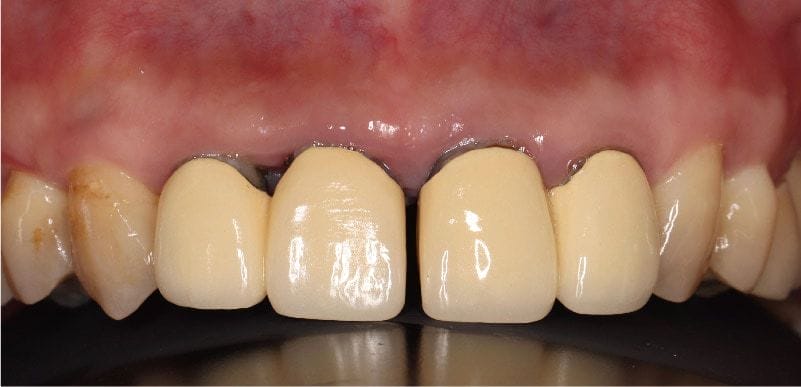

他舊有的門牙假牙,剛製作時並沒有縫隙,而是後來才越來越明顯而影響外觀。其實這在牙周病或是缺牙患者很常見,問題根源在於,因嚴重牙周病會導致牙齒沒有辦法負擔咬合力量,或是臼齒缺牙後未重建而習慣用前牙咀嚼。

若是前牙本身牙周支撐力量不足,甚至還承擔臼齒缺牙的咬合力量時,這樣會使前牙發生咬合傷害(occlusal trauma),產生病理性位移(pathologic migration)現象,這導致門牙產生間隙,並且越來越突出,形成暴牙影響外觀。其實很多人並不清楚這是牙周病的症狀與後遺症之一。

圖示:舊門牙假牙位移產生縫隙,且突出形成暴牙,是典型的牙周病症狀與後遺症